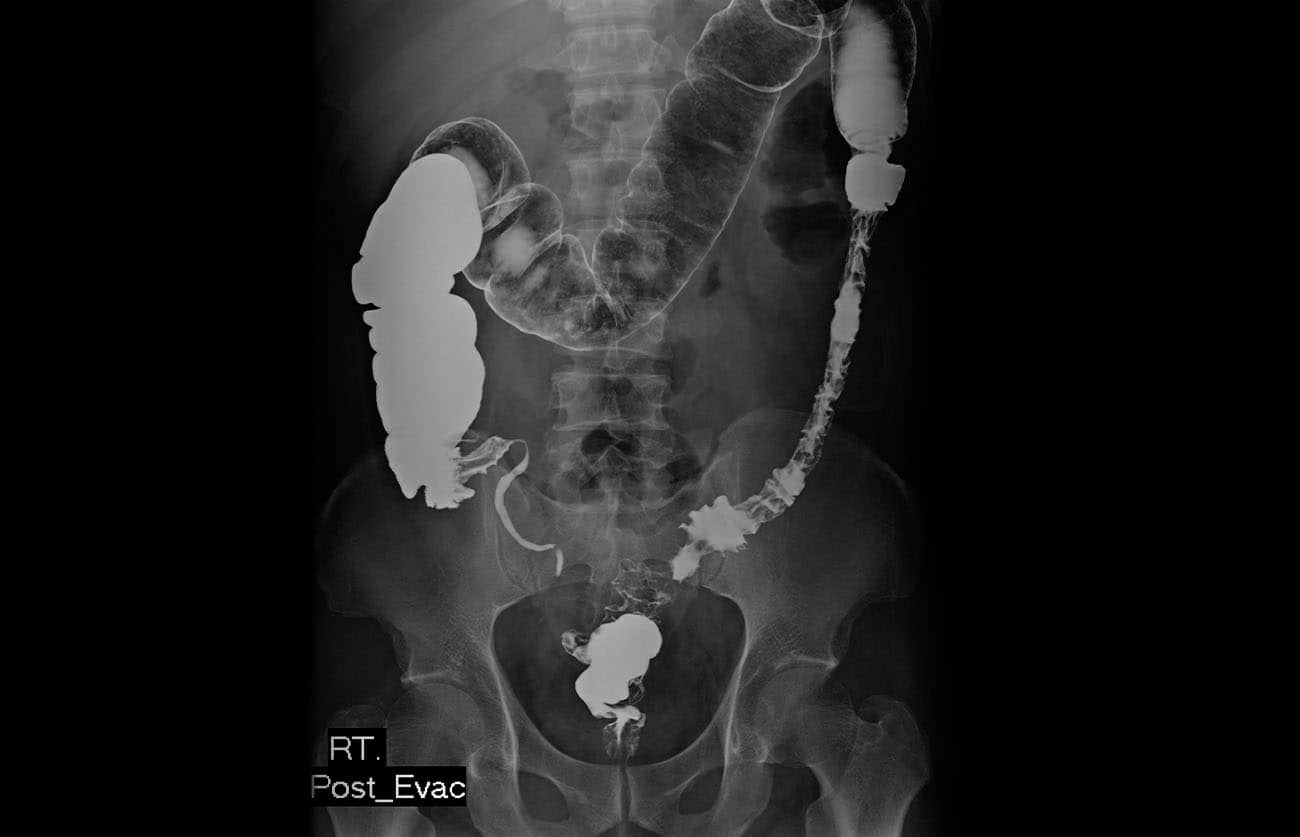

Incidência PA ou AP – Pós-evacuação: enema baritado

Enema baritado na fase de pós-evacuação.

Justificativa para realização do exame

Visualizar os padrões da mucosa do intestino grosso com resíduo de contraste para estudo de pequenos pólipos e defeitos.

Principais estruturas demonstradas

Todo o intestino grosso, com contraste residual.

Fatores técnicos e posicionamento

• DFF: 1m.

• Tamanho do filme/receptor de imagem e sentido: 35x43cm no sentido longitudinal.

• Técnica de referência: 4mAs e 100 KV, na mesa.

• RC: perpendicular no centro do filme e ao nível das cristas ilíacas.

• Posição do paciente e da parte ou região do corpo: paciente em decúbito ventral ou dorsal, com os braços para cima, fornecendo um travesseiro para o rosto, que deve ficar de lado.

• Respiração: parar a respiração e expor durante e expiração.